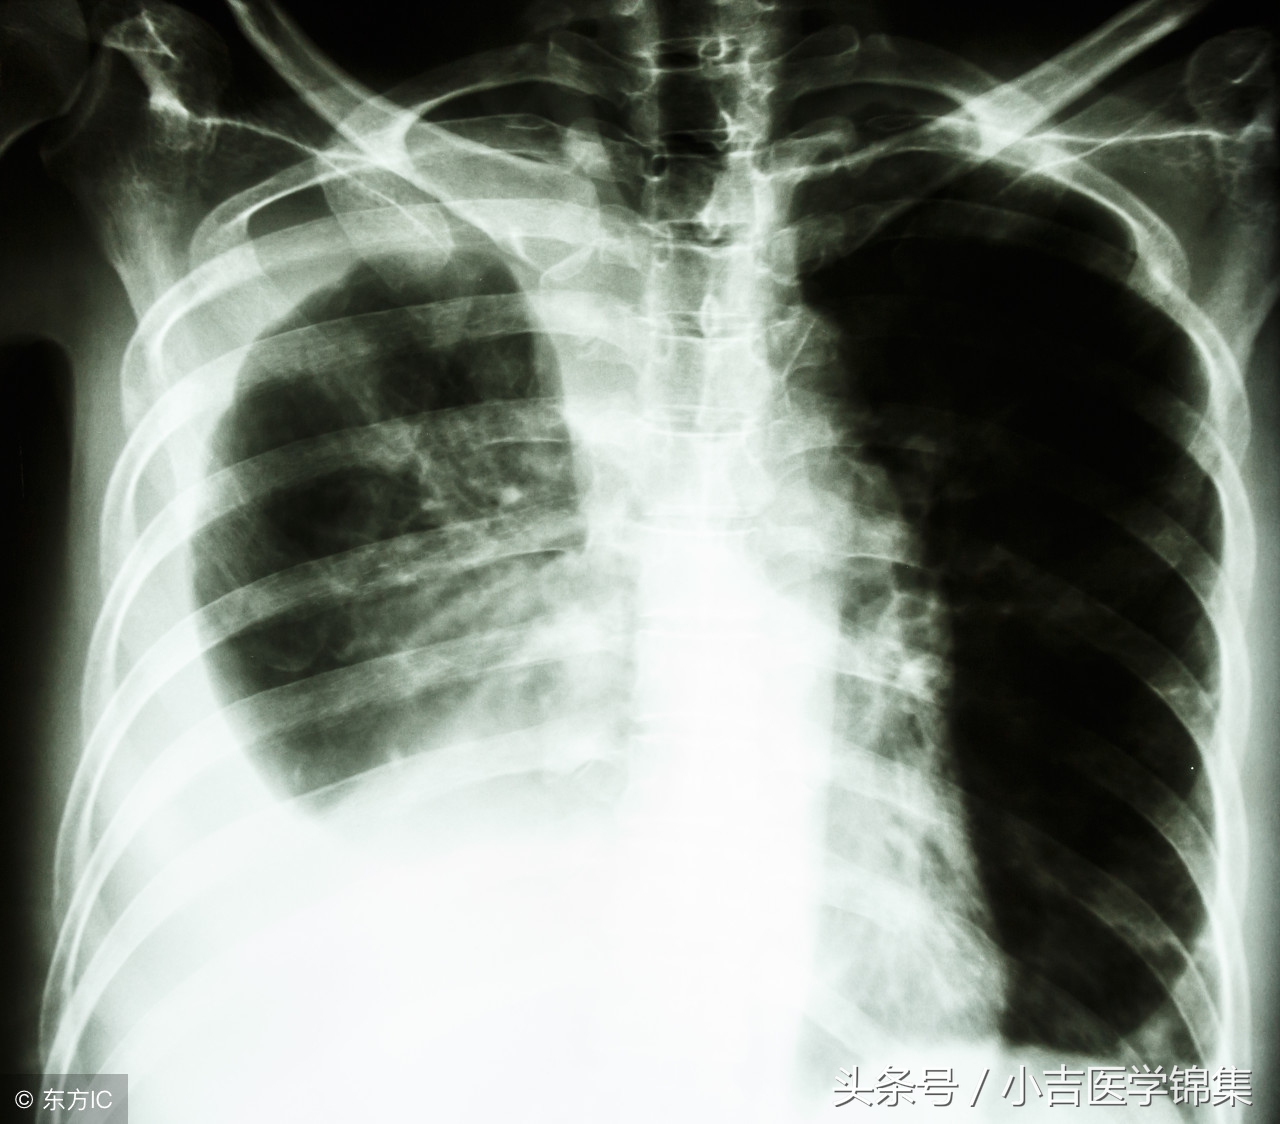

1、胸部X线:在胸片上判断胸腔积液的标准为:在第4前肋间以下为少量胸腔积液,第4前肋与第2前肋之间,属于中等量胸腔积液,积液位于第2前肋以上者,为大量胸腔积液。

⑵积液量300-500ml,可出现肋膈角变钝。

⑶积液量>500ml,表现为凹面向上,外侧高内侧低的弧形积液影。

⑸包裹性积液:可发生于胸腔任何部位,以叶间积液多见,呈梭形,不随体位改变而变动,边缘光滑饱满。